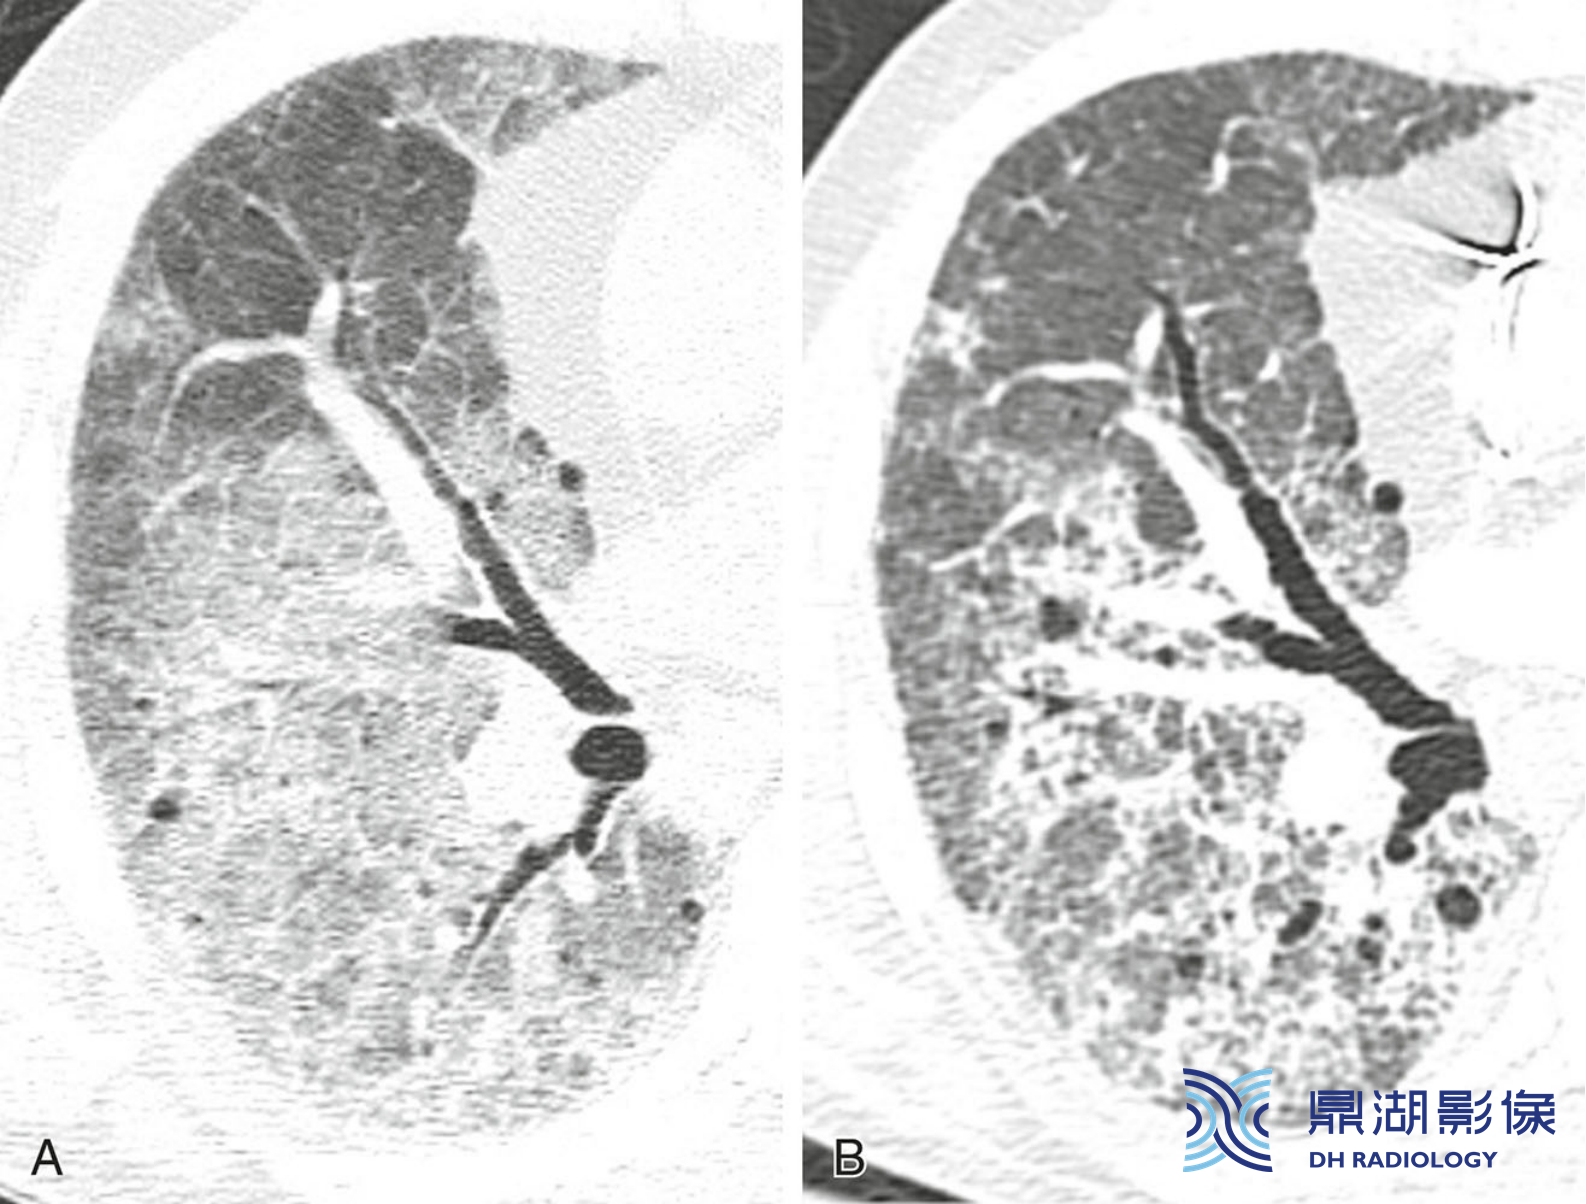

46dfcd824cef79e6089ab6e0910440fd.png

弥漫性肺泡损伤(DAD)。CT ( A)显示广泛的GGO。3周后(B)小叶间隔发展为不规则网状影并可见牵拉性支气管扩张。这是DAD随时间推移的典型演变过程。